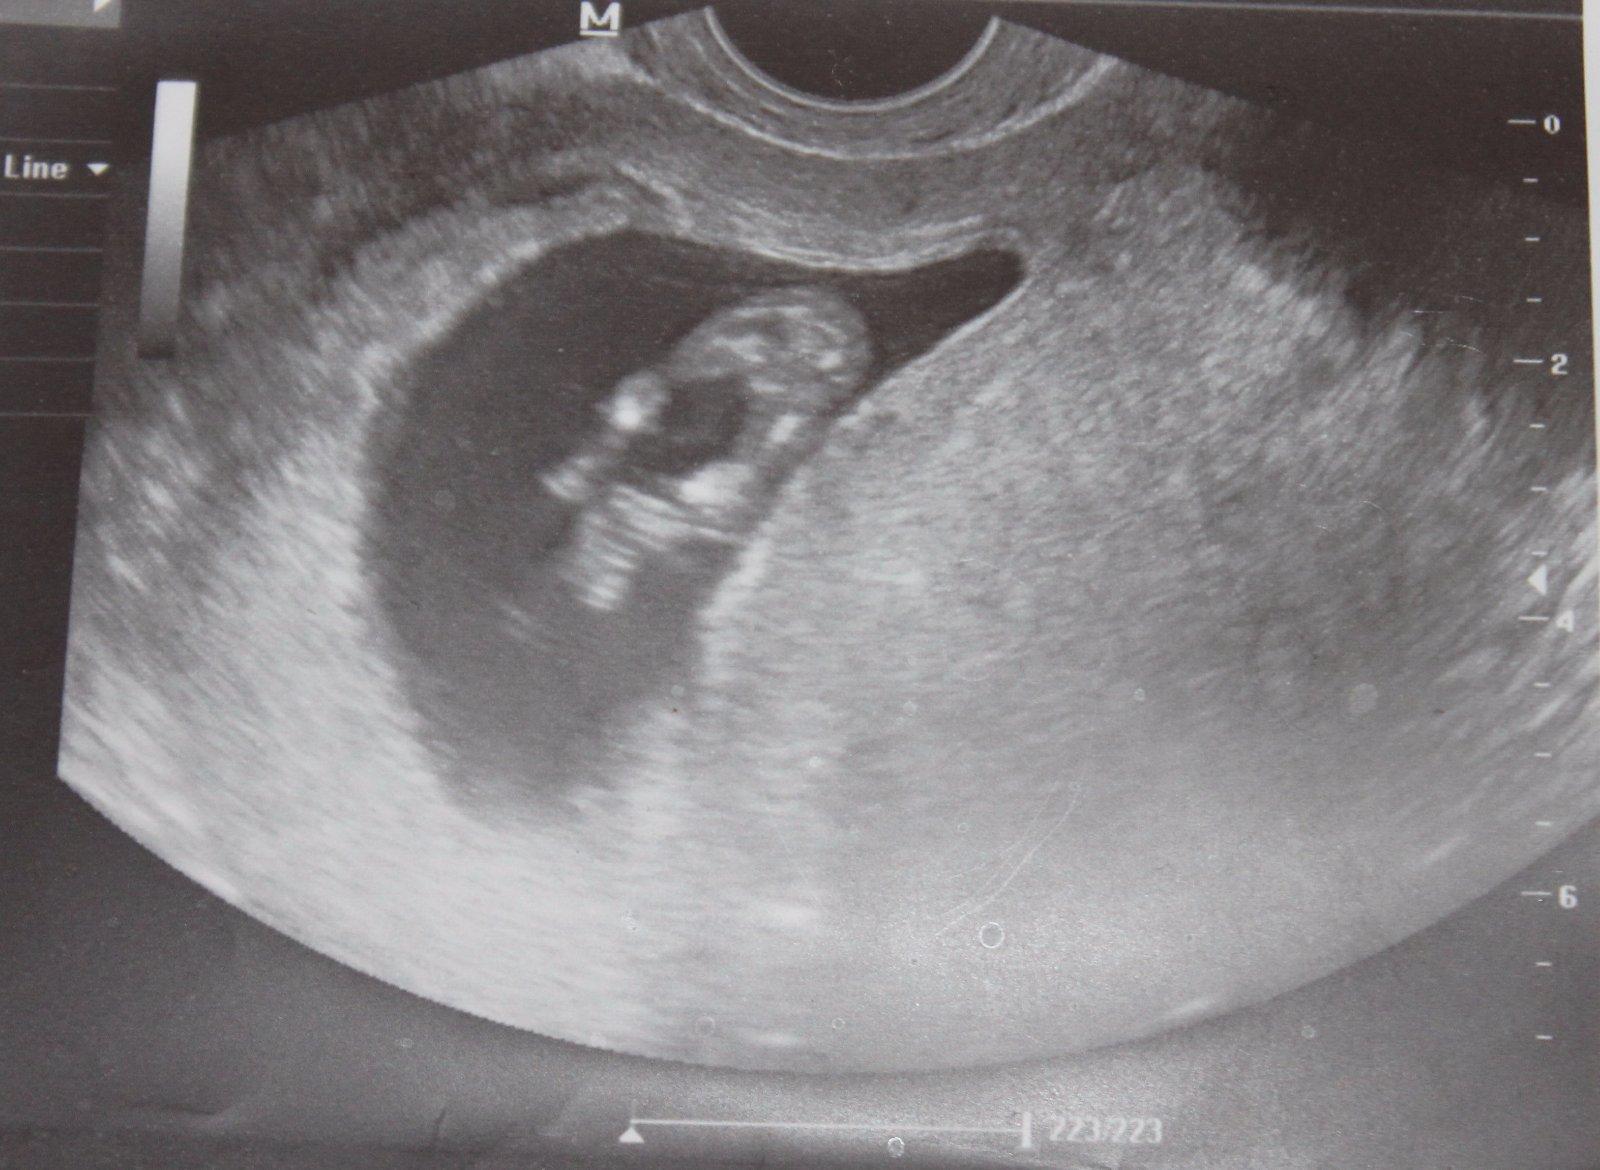

Vidíte na tejto fotke jedno alebo dve bábätka?

Ahojte maminy a cakatelky, prosim vas pekne, zda sa to iba mne alebo vidite na obrazku z UZ viac ako jedno babatko? dve fotky vytvorene tesne po sebe a na prvej vidim vpravo v hornom rohu (akoby za ciernou dutinou) babatko spredu (hlavicka a lava rucicka) a hned na druhej zozadu akoby stavce, hlavicku a svetle "ciarky" - nozicky. Totiz cim viac to pozorujem, tym viac neviem na com som. Podla mna sa pocas "fotenia" otocilo lebo aj to prve sa velmi rychlo stale hybalo. Prosim vidi este niekto okrem mna viac ako jedno dietatko ci nie? dakujem za vase nazory, DAKUJEM velmi velmi!

PS to dietatko ( aj ked vidno iba jeho cast) v strede v tej tmavociernej casti je iste a potvrdene doktorom... ;)

no doktor videl to jedno co je v tej ciernej dutine. a ked som prisla domov a prezrela to leporelo co mi vytlacil zbadala som tam hned na prvej spredu dalsie a na druhej fotke akoby sa otocilo a chrbatik so stavcami. tak preto chcem vediet ci som jedina co ho tam vidi... k doktorke idem az o 2 tyzdne zasa...

@trgypadl UZ bol robeny v 12 tyzdni. mozem nahrat celu fotku, toto je len vyrez. mozno toukaze lepsie. o chvilku to nahram...

na obidvoch fotkach vidim to druhe babatko vpravo hore v rohu akoby (nie v tej dutinke kde je prve!) Za tym druhym babom na druhej foto aj cierne pozadie, akoby to babo bolo na kraji dutinky druhej... ale je mozne ze sa iba mylim. vobec netusim na com som a to cakanie ma iba nici ☹

daj celu fotku 🙂 a aj pripis, ktory je to tyzden. Ale ako pisali baby vyssie, ak by boli dve, lekar by to videl. Alebo pocul,ze tlcu 2 srdiecka....(teda neviem, v ktorom tyzdni si ) ale Kamaratka je v 7tt a caka dvojicky, jednovajecne, v jednom vaku su obe, a uz to lekar videl aj ked je len v 7tt. Cize neviem, tie foto su vo velmi zlej kvalite, ale ja vidim tiez len jedno babatko 🙂